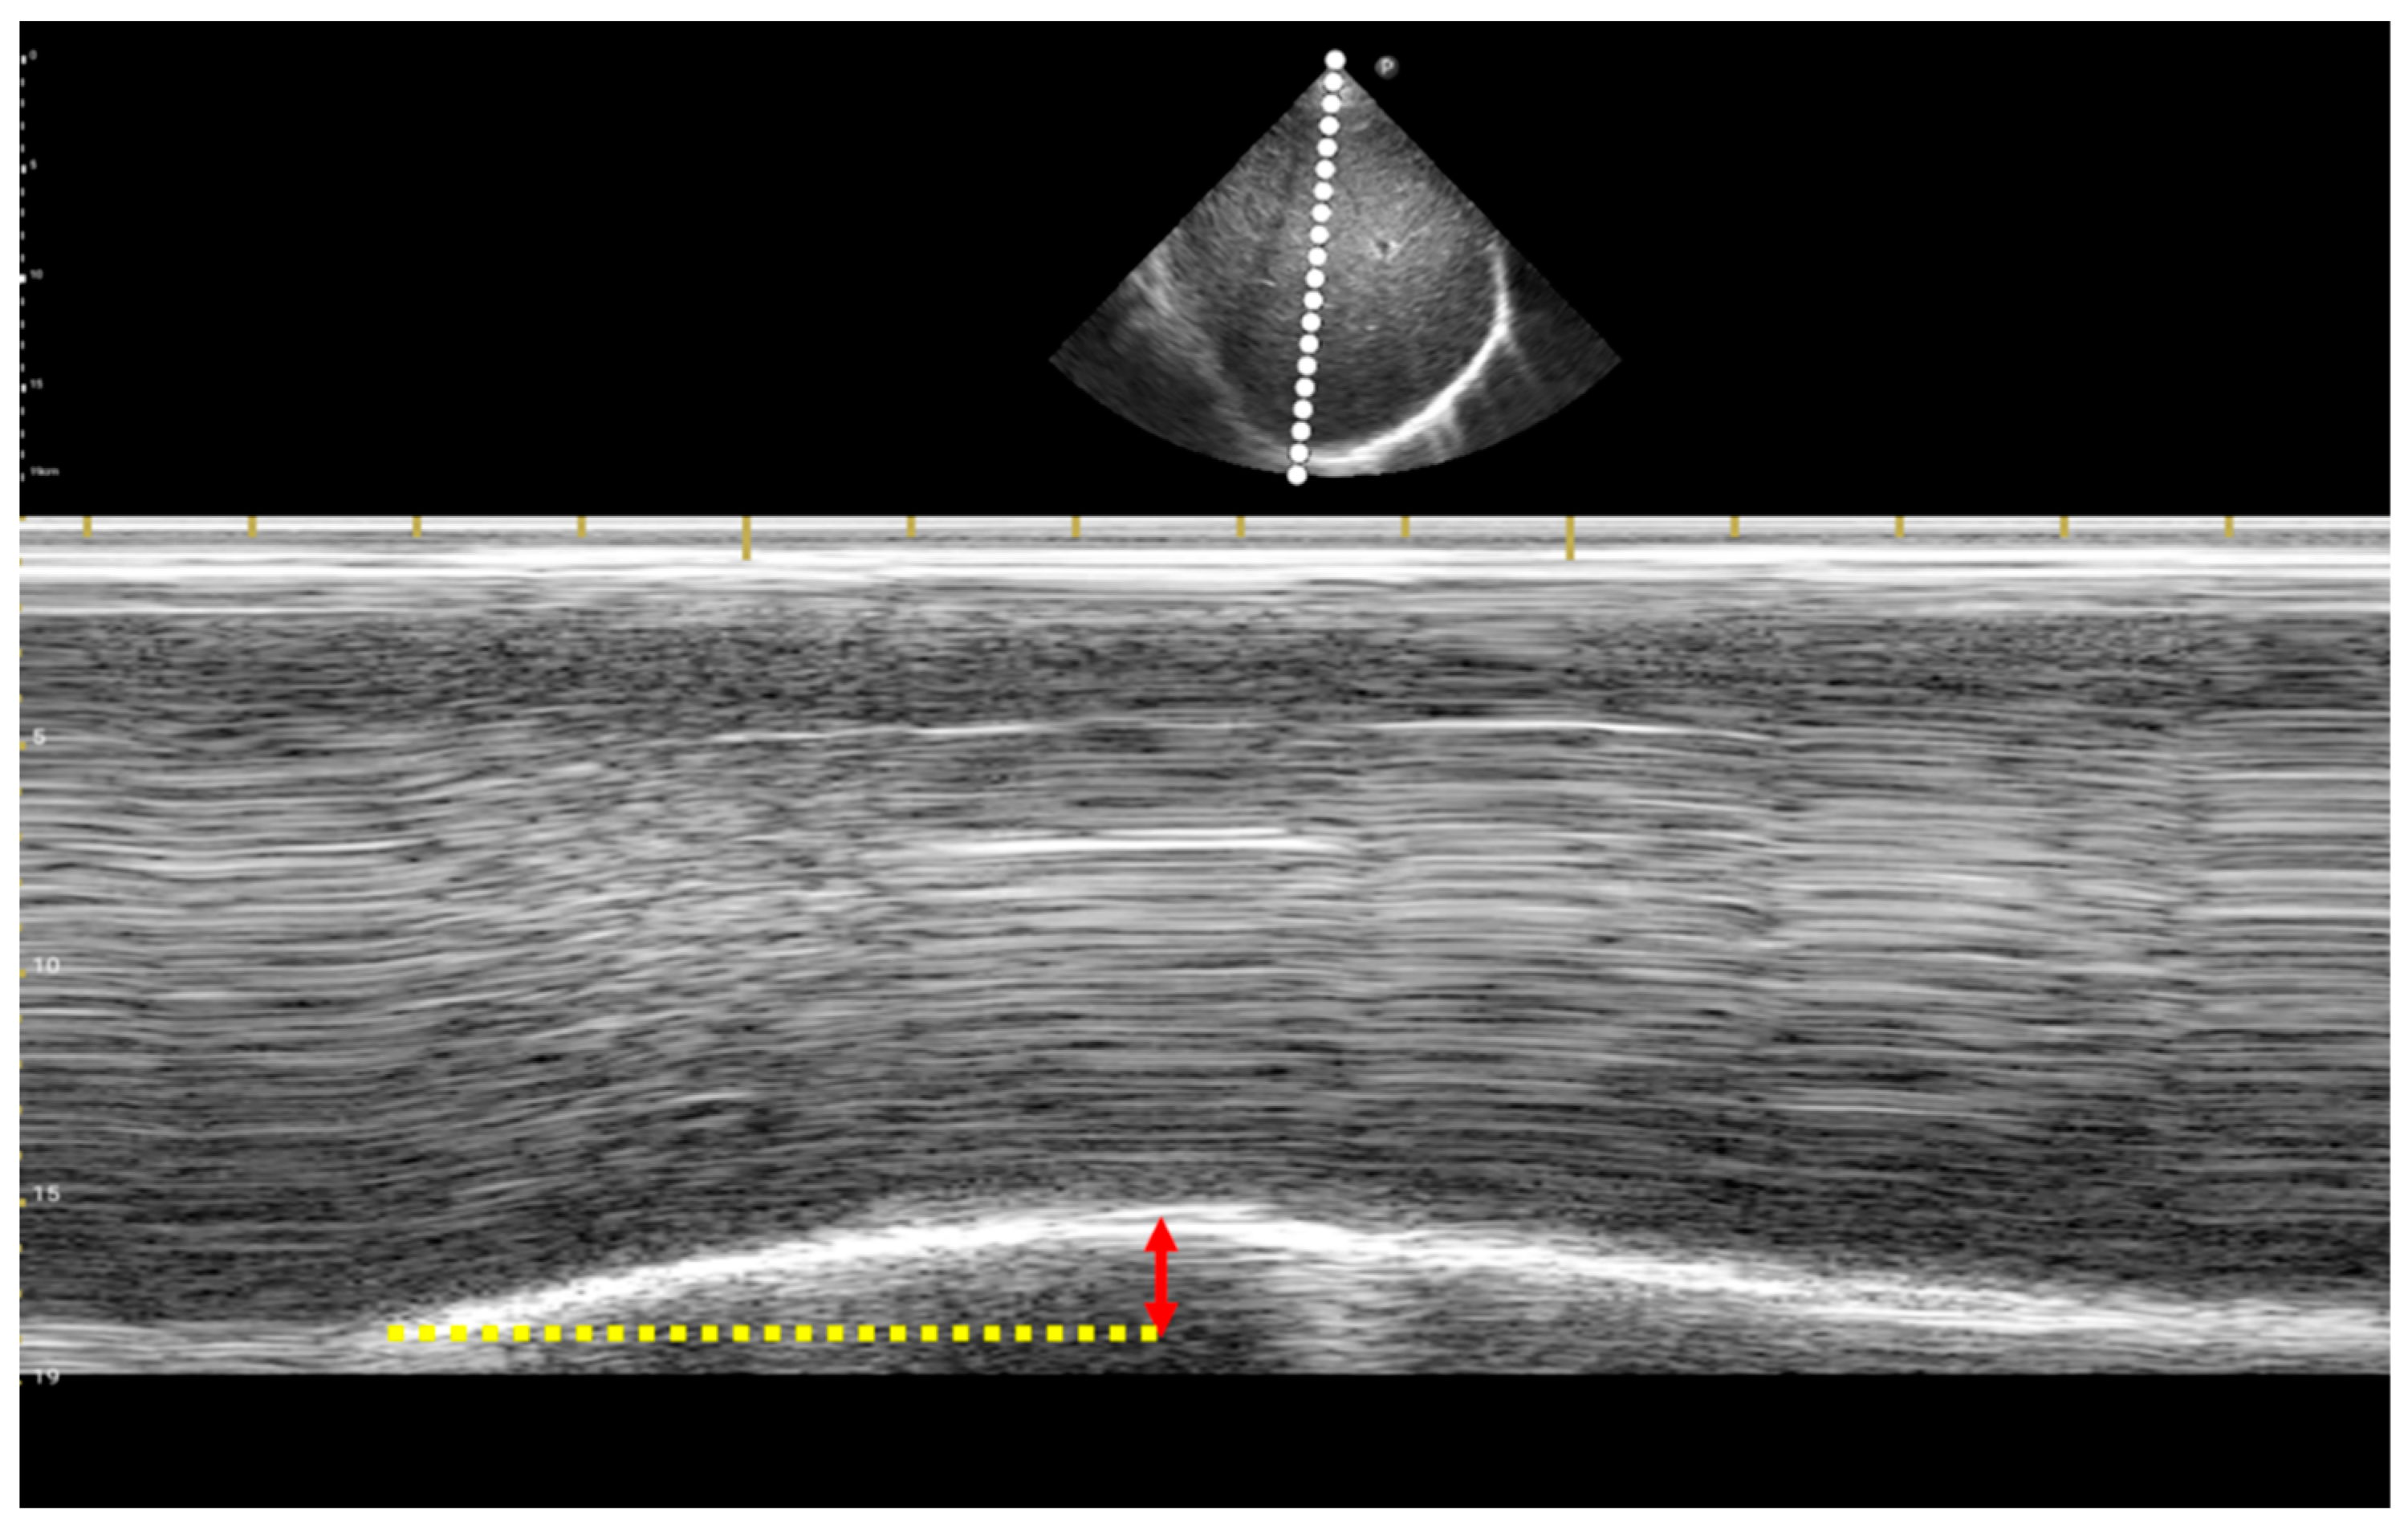

2.2. Procedure of Lung Ultrasound and Measurement of Lung Ultrasound Indices

| DTF | diaphragm thickening fraction |

| D-RSBI | respiratory rate divided by half the sum of the right and left diaphragmatic displacement |

| DTi-RSBI | respiratory rate divided by the product of diaphragmatic displacement and diaphragm inspiratory time |

| Ti | diaphragm inspiratory time |